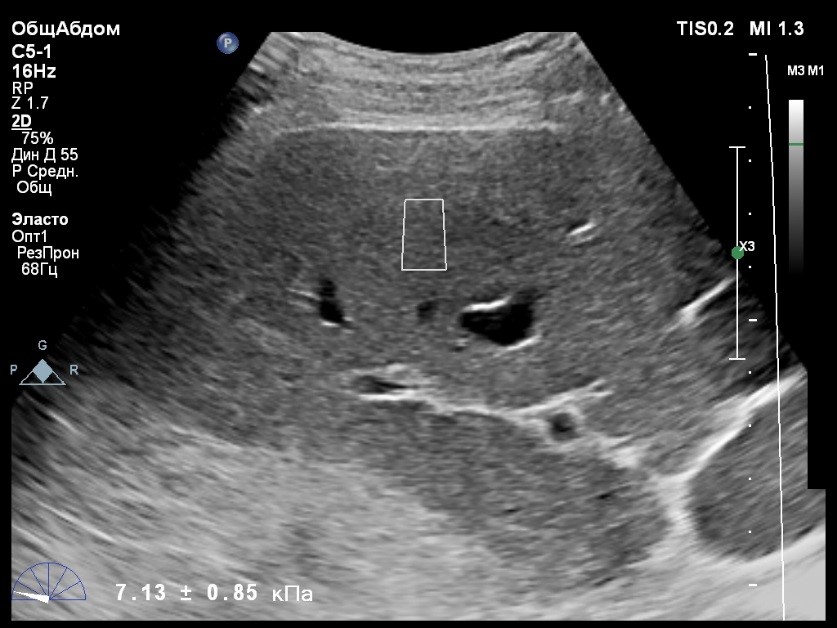

Пациент обратился к доктору с направлением на исследование степени жесткости печени в июне 2017 года. Из истории болезни, пациент страдает Гепатитом С с 2015 года. Лечение не получал. В апреле 2016 года, с помощью транзиентной эластографии была установлена медиана жесткости печени 5,8 kPA (4,4-7,7). На момент настоящего исследования, пациент не принимал пищу на протяжении 4 часов, АСТ, АЛТ не превышают патологических значений. Для оценки жесткости была выбрана технология компании Philips ElastPQ (точечная эластография) и прибор компании Philips Epiq 7 Исследование было проведено в соответствии с клиническими рекомендациями для ультразвуковых приборов компании Philips. В результате исследования были получены следующие результаты:

| 1 [4.94] kPa | 2 [7.09] kPa | 3 [7.13] kPa |

| 4 [4.74] kPa | 5 [5.17] kPa | 6 [7.78] kPa |

| 7 [6.19] kPa | 8 [7.63] kPa | 9 [4.64] kPa |

| 10 [6.18] kPa | 11 [4.49] kPa | 12 [4.54] kPa |

| 13 [6.08] kPa | | |

Стандартное Отклонение [1.17] kPa Медиана Жесткости [6.08] kPa Фактор Качества IQR/Med 9%

Зона интереса расположена на более чем на один сантиметр глубже капсулы, параллельно ходу луча, в середине изображения, в участке печени лишенном артефактов.

Капсула видна как белая линия перпендикулярная ходу ультразвукового луча, исследования производятся приблизительно в одном и том же сегменте печени.

Стандартное отклонение (0,96 kPA) не превышает 30 процентов от полученного значения (4,54 kPA).

Зона интереса расположена вне крупных сосудов.

Для интерпретации полученных клинических данных были использованы Рекомендации по проведению эластографии сдвиговой волной для оценки жесткости печени при использовании ультразвуковых аппаратов компании Филипс с примером протокола. Анамнез основного заболевания пациента достаточно короткий и показатели жесткости печени, полученные в 2016 свидетельствуют об отсутствии значимых фиброзных изменений. Однако, в течении всего времени пациент не получал специфического лечения. Данный факт является показанием для динамического наблюдения и оценки жесткости печени. Подготовка пациента соответствовала проводимому исследованию. Представленные слайды проведенного исследования свидетельствуют о правильном техническом исполнении проб, что позволяет заключиться о достоверности полученных измерений. Таким образом, учитывая полученную медиану жесткости на уровне 6.08 кРа (4.49 – 7.78 kPa) и уровень стандартных отклонений не превышающих 30%, полагаю, что уровень степени фиброза соответствует стадии F 0-1. Заведующий отделением УЗД МЦ «Асклепий», Глушенко Д. Е.